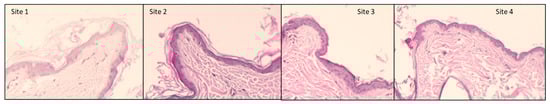

2.3. Evaluation of the Depth of Remaining Stratum Corneum

| Thickness (µm) | Dog 1 | Dog 2 | Dog 3 | Dog 4 | Dog 5 | Dog 6 | Dog 7 | Mean |

|---|---|---|---|---|---|---|---|---|

| Site 1 | 15.89 | 21.98 | 36.72 | 16.08 | 13.74 | 17.68 | 16.15 | 19.7485714 |

| Site 2 | 11.91 | 18.22 | 16.36 | 14.85 | 14.28 | 11.93 | 12.72 | 14.3242857 |

| Site 3 | 6.38 | 3.29 | 5.1 | 4.06 | 6.44 | 8.34 | 5.15 | 5.53714286 |

| Site 4 (number of D-squames®) | 8.19 (29) | 5.4 (50) | 7.28 (42) | 8.12 (46) | 8.53 (42) | 10.09 (41) | 7.16 (29) | 7.82428571 (39.85714) |